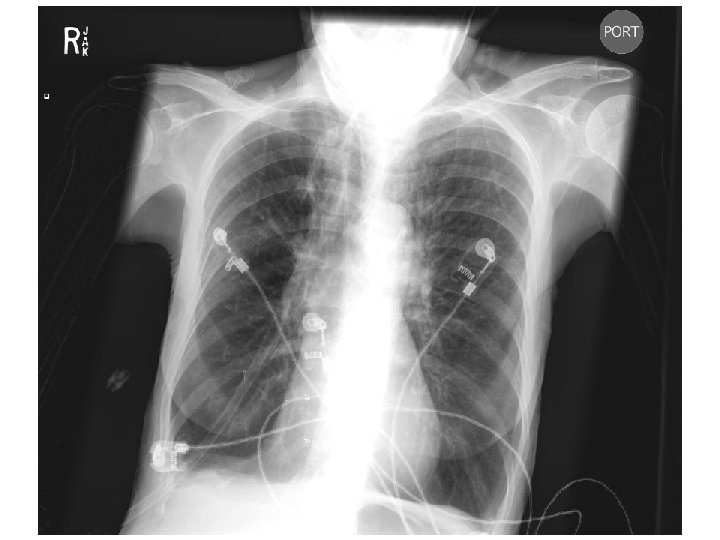

Special Studies-2 Imaging studies Ventilation-perfusion lung scan Chest CT, HRCT (high resolution CT) Gallium scanning Diaphragmatic fluoroscopy